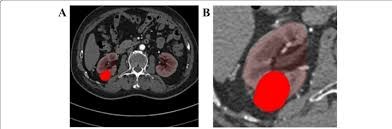

o Ultrasound: Initial screening for cysts/masses.

o CT Scan: Detailed X-ray images to explore tumors, size, spread.

o MRI: Detail soft tissue imaging, usage when CT was not ideal.